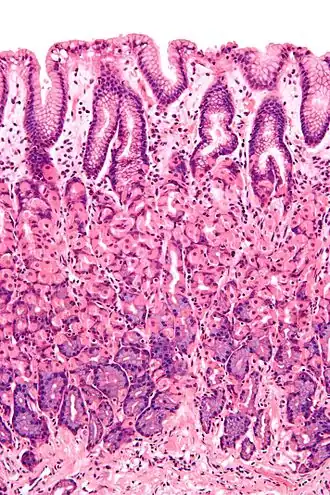

Microscopic section of gastric mucosa. Foveolar cells can be seen at top of the image lining the surface and pits | |

Foveolar cells or surface mucous cells are mucus-producing cells which cover the inside of the stomach, protecting it from the corrosive nature of gastric acid.[1][a] These cells line the gastric mucosa and the gastric pits. Mucous neck cells are found in the necks of the gastric glands. The mucus-secreting cells of the stomach can be distinguished histologically from the intestinal goblet cells, another type of mucus-secreting cell.

The gastric mucosa that lines the inner wall of the stomach has a set of microscopic features called gastric glands which, depending on the location within the stomach, secrete different substances into the lumen of the organ. The openings of these glands into the stomach are called gastric pits which foveolar cells line in order to provide a protective alkaline secretion against the corrosive gastric acid.[2]: 256

Foveolar cells line the surface of the stomach and the gastric pits. They constitute a simple columnar epithelium, as they form a single layer of cells and are taller than their width. Other mucus-secreting cells are the mucous neck cells in the necks of the gastric glands.[2]: 257